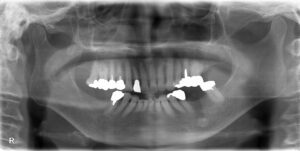

まずは初診時の写真、レントゲンです。

【初診時】

上記のように、入れ歯を長年使用されておりましたが、右下の歯が痛くて噛めないとのお悩みを抱えていらっしゃいました。

そこで全体的に検査を行い、以下に当院での診断結果です。

【診断結果・治療方針】

①右下の歯が動揺しており、長年の入れ歯の使用・かみ合わせのせいで負担がかかり、破折している。

→実際に被せをとって確認し、患者様にも写真で確認して頂いました。

②まずは入れ歯の使用をしないように指示。

→直後から痛みが消失しました。

③右下の歯は抜歯が必要。ただ、奥歯にしっかりとかめるものをいれる必要があるので、インプラント治療を行う。また、左下奥歯は、保険でブリッジの治療を行う。それによって、入れ歯を使用することなく、今までより痛みなく、食事が可能である。

→先に右下インプラント埋入。その後、左下処置行った。